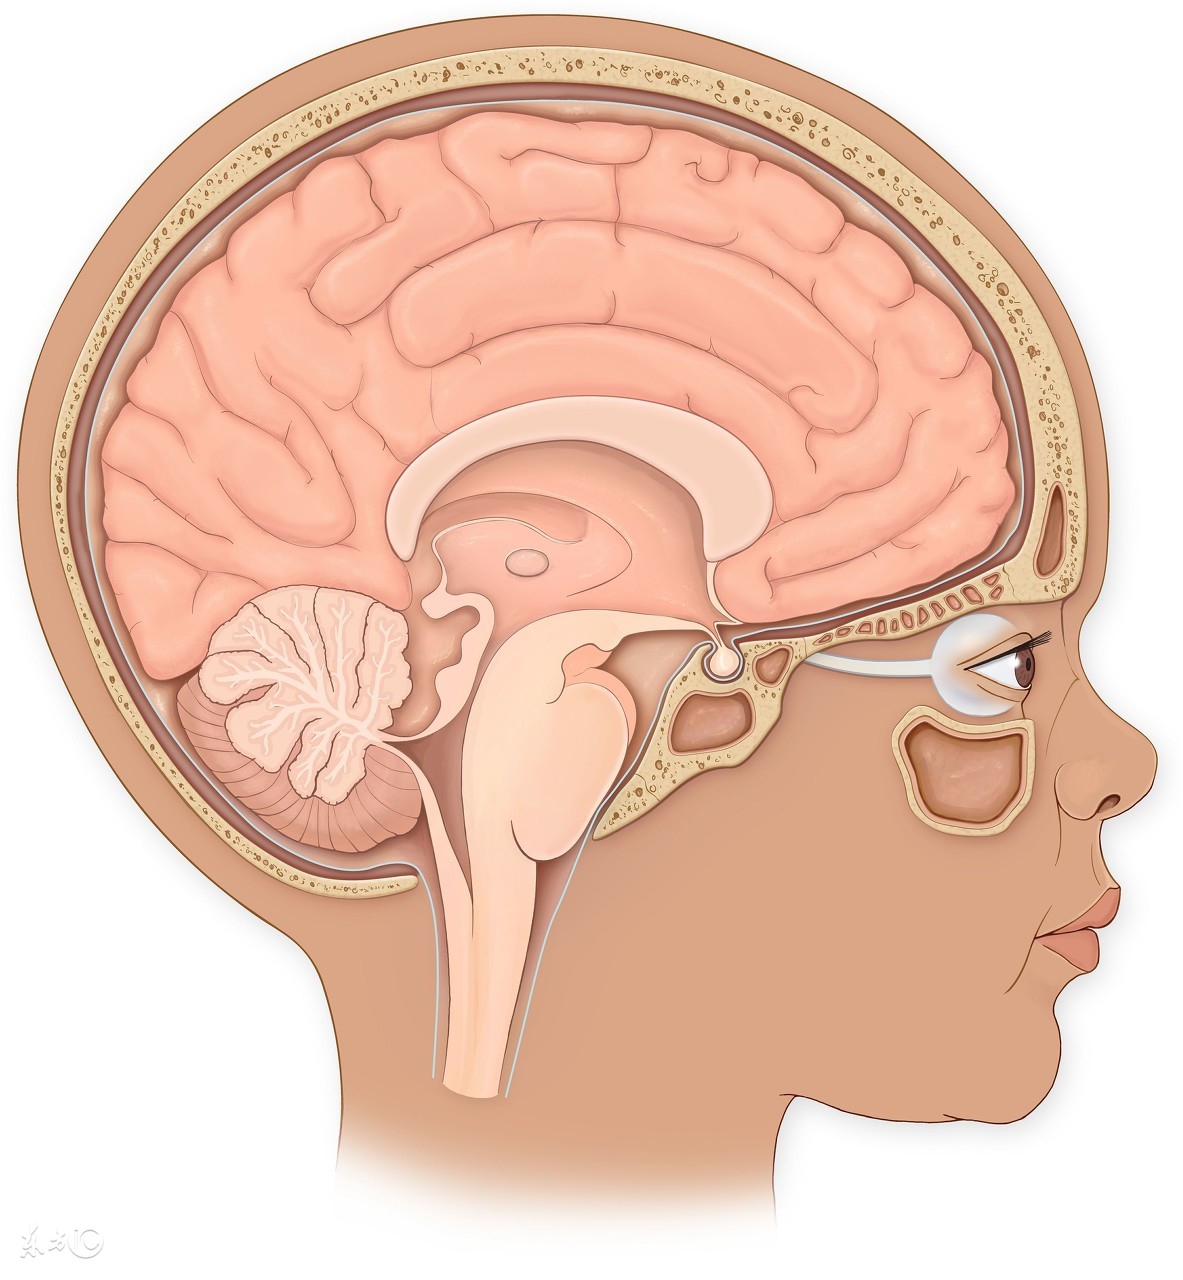

病理性手抖,医学上称为“震颤”,是指手不随意地颤动,常为永久性的,其病根可能是由于某种疾患使大脑涉及运动协调功能的区域受到损害。

4、小脑病变。小脑参与躯体平衡和肌肉张力的调节,以及随意运动的协调,一旦小脑发生病变,患者会出现意向性震颤,即患者越接近目标物体,其抖动越明显。此外,还可出现眼球震颤、言语改变以及站立行走不稳等共济失调的表现。